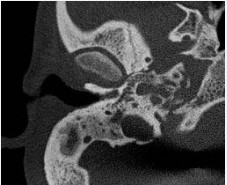

Aural discharge was sent for culture, found sterile. Highresolution computed tomography (HRCT) of temporal bone showed soft tissue opacification and expansion of mastoid and petrous air cells (Figure 1).

Figure 1: (Patient 1) High-resolution computed tomography (HRCT) of temporal bone (right) showing soft tissue opacification and expansion of mastoid and petrous air cells without any evidence of bony erosion.